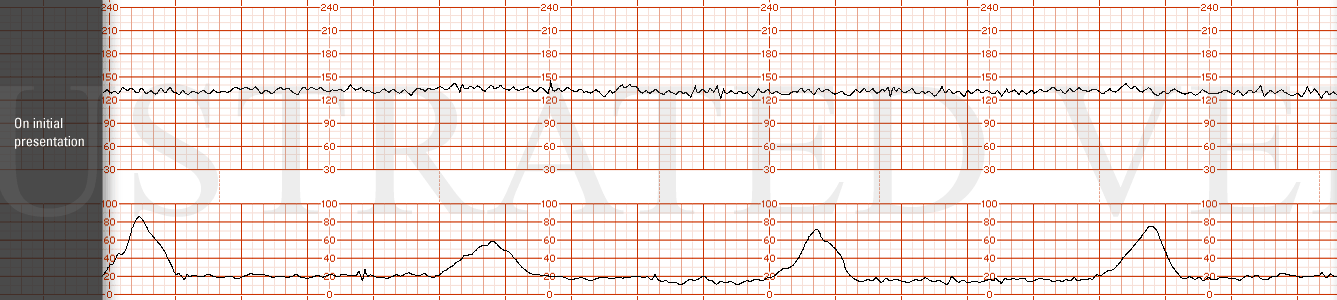

STRIP 69

1. Panel 20 minutes

Nine contractions, each 50-60 sec long, in last 20 minutes. 2nd, 3rd and 4th contraction to long, about 10 secs, 6th needs 15 secs off,

Baseline rate at +/- 150 bpm over 20 minute panel with minimal variability

Three mild-moderate variable decelerations - (varying in duration from20-35 sec each to nadir varying between 105 to 120 bpm ( 4, 10 (needs to be moved over 1 min) and 16 (move 30 secs over to right) minutes in the 20 minute segment). There is no progression in depth or duration of the decelerations - random

There is one 18-bpm acceleration at minute 8-9 in the last 20 minutes

Category 2 with mild to moderate variable decelerations and minimal variability.

STRIP 70

1. 1st panel:

Tracing to show 140 bpm with average variability and no decelerations. Five 50-second contractions noted in 20 minutes of observation. (1st and 2nd contraction 10sec less, 5th 30secs less

2nd panel:

Panel: 20-minute of FHR strip.

Contractions:11 in 20 minutes, each lasting +/- 50-55 seconds. (1st 3rd, 4th, 6th, 7th, 8th, 10th and 11th too long 10-15 secs off)

Baseline +/- 165 bpm with minimal variability

Four mild to moderate, (but not unusual variable decelerations down to range of 105 to 125 bpm at minute 4, 11, 17 minutes, each with duration varying between 25-35 seconds.- with prompt return to baseline. There is no progression in depth or duration of decelerations – random. (1st 2nd more abrupt, 1st deeper, 4th more abrupt and deeper)

There are no spontaneous accelerations.

Indicate scalp stimulation at minute 18 with no resultant acceleration